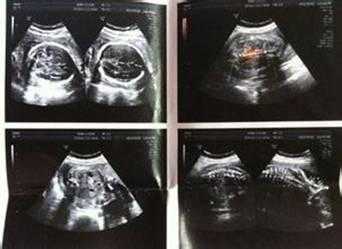

云小派上传b超单吗?

云小派上传b超单。

云小派是上海一榛科技有限公司开发的专注于礼品福利的派发的服务程序,对象是孕妈妈和宝妈,上传b超单没有风险。